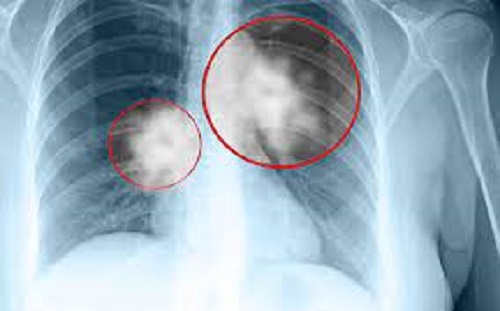

• Những người bị ho ra máu thường được chụp X-quang ngực hoặc chuyển đến bác sĩ chuyên khoa về rối loạn ngực. Ung thư phổi thường xuất hiện dưới dạng khối màu trắng hoặc xám trên tia X. Tuy nhiên, có thể khó phân biệt giữa khối u và áp xe phổi, có nghĩa là chụp X-quang không phải là xét nghiệm xác định. Khi khối u lộ ra, bệnh nhân được giới thiệu đến bác sĩ chuyên khoa phổi, người sẽ tiến hành các cuộc điều tra chi tiết hơn để kiểm tra xem có phải ung thư phổi hay không và mức độ tiến triển của nó.